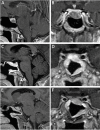

Acromegaly is a disease that occurs secondary to high levels of GH, most often from a hormone-secreting pituitary adenoma, with multisystem adverse effects. Diagnosis includes serum GH and IGF-1 levels, and obtaining an MRI pituitary protocol to assess for a functional pituitary adenoma. Attempted gross total resection of the GH-secreting adenoma is the gold standard in treatment for patients with acromegaly for a goal of biochemical remission. Medical and radiation therapies are available when patients do not achieve biochemical cure after surgical therapy.